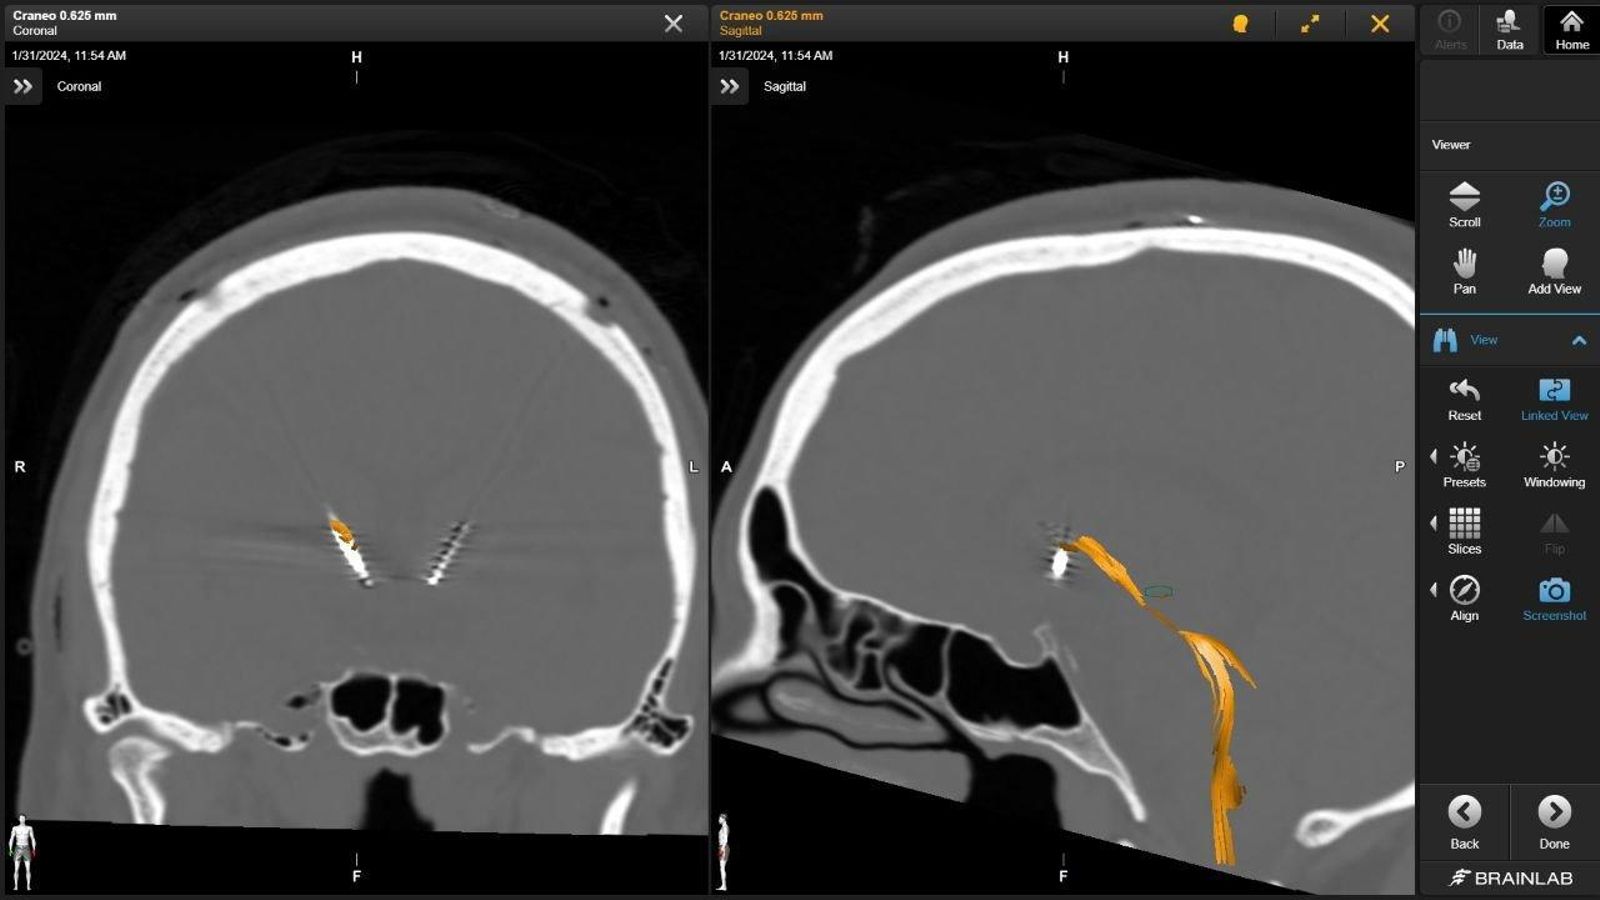

Así se veía el cráneo del paciente con TOC.

Los neurocirujanos que coordinaron la operación, Pablo Sousa y Laura Serrano, explican que “la intervención consiste en la implantación de dos electrodos profundos, uno en cada hemisferio cerebral, de una manera mínimamente invasiva, a través de pequeños orificios en el cráneo. Estos electrodos están conectados a una batería subcutánea que situamos bajo la clavícula del paciente, y producen impulsos eléctricos en una diana muy concreta del cerebro. El resultado es que estas descargas inhiben el circuito cerebral. El objetivo es reducir al máximo la sintomatología del trastorno, cambiando la actividad cerebral de una manera controlada”.

El sistema se compone de una batería que se coloca bajo la piel y de la que salen dos cables que tienen unos electrodos en la punta. Son como ocho contactos metálicos que transmiten la corriente eléctrica en la zona en la que están situados, en este caso en una zona profunda del cerebro en la que hay un circuito que no funciona como debe. Los electrodos frenan la corriente eléctrica aplicada sobre las neuronas y lleva a ese circuito a una situación de equilibrio. Además, también introduce cambios en zonas que funcionaban por debajo de su actividad normal.